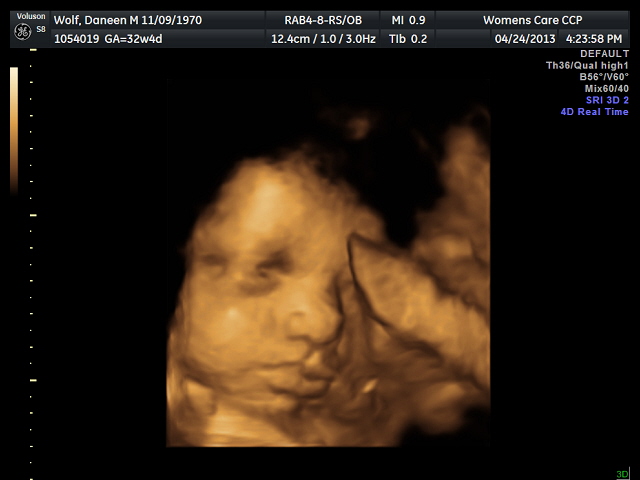

| Happy Girl |

The one good thing about having a baby in your

forties is that you have more ultra sounds. I just had our 32 week ultra sound which was

amazing. I could have stayed in the room

all day watching my baby girl kick, open her eyes, and suck her fingers. She

was wide awake and moving all around during the process.

The ultra sound tech was fascinated by her expressions

that she took a total of 15 pictures for us to keep rather than the 3 or 4 that

most people receive.